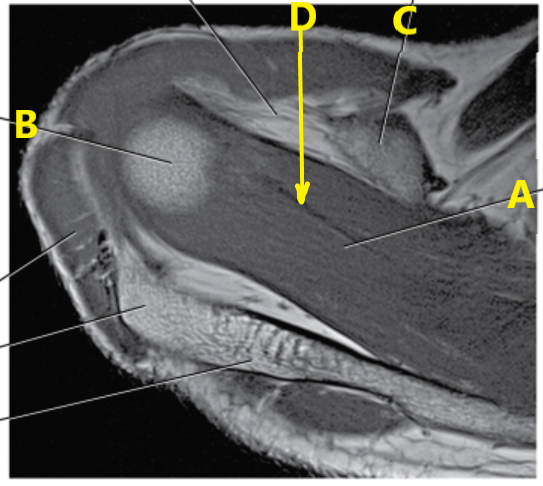

What is this special view of the shoulder joint called ?

Abduction external rotation

What is letter A pointing to ?

Supraspinatus muscle

What is letter a?

Biceps brachii tendon

Subscapularis tendon

What is letter c ?

Posterior glenoid labrum

What is letter d ?

Scapular spine

What images will be created with this slice prescription ?

oblique coronal

What is # 3 ?